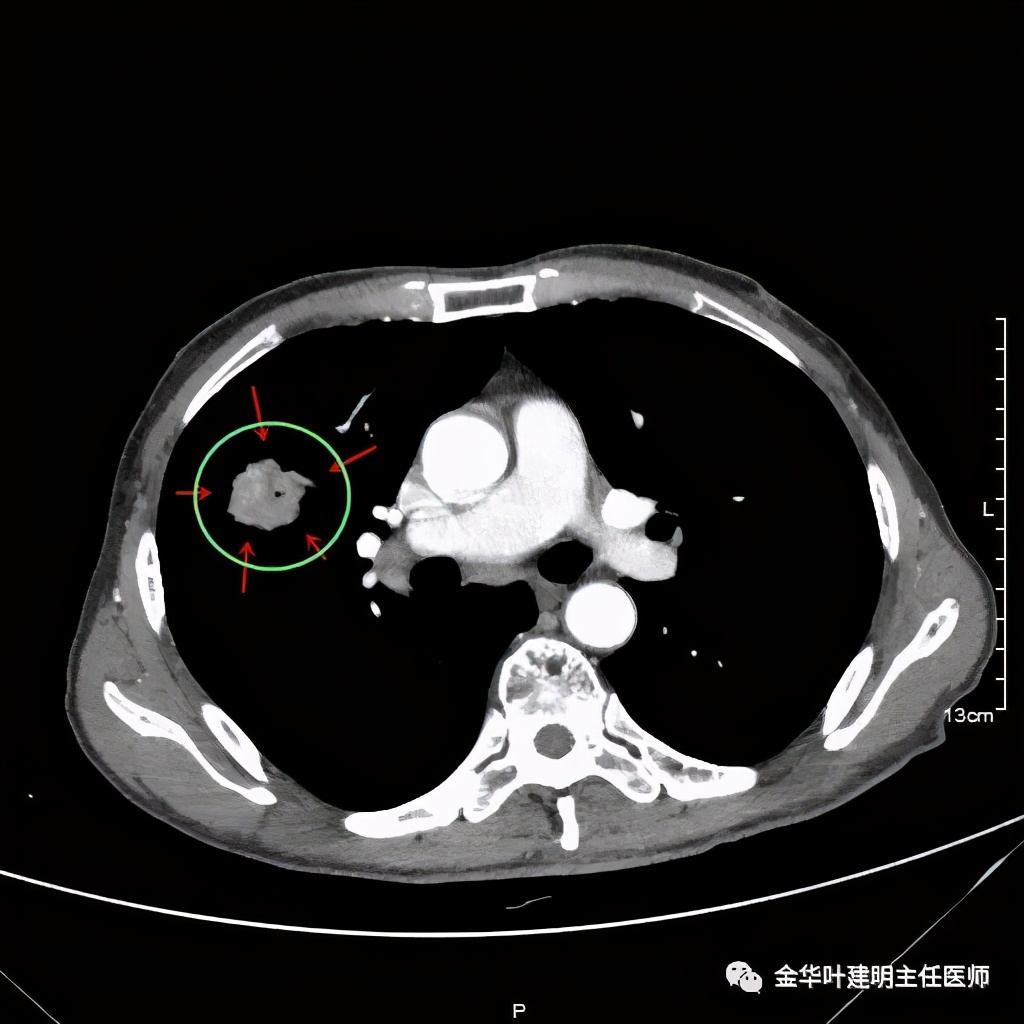

金华的某A,今年73岁,男性。检查发现右上肺占位,肿瘤筛查指标正常,血常规与CRP正常,临床有反复咳嗽、咳痰2年余(考虑慢支的关系,近期也许同时有病灶的影响)。一年前还在外院做过支气管镜,也未见确切异常。我们先来看他这次的胸部CT图像:

上图示病灶

上图示病灶边缘不太光整,内部密度不太均匀

上图紫色箭头示叶间胸膜受牵拉,病灶边缘部分见到细毛刺